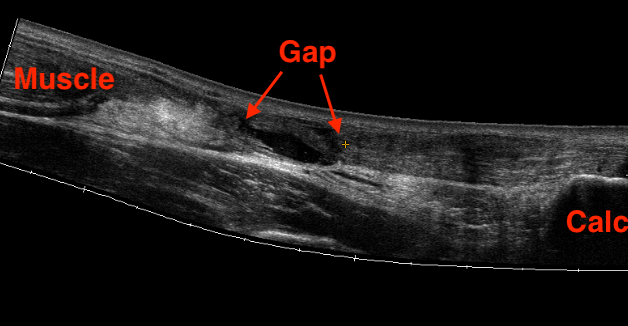

Ultrasound

Diagnose rupture and check reduction of tendon ends with plantarflexion

Aminlari et al J Emerg Med 2021

- systematic review

- ultrasound 95% sensitive and 99% specific for complete rupture